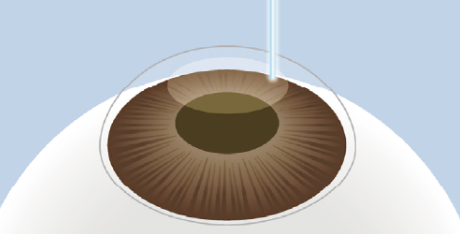

レンチクルの形成

フェムトセカンドレーザーを使用し、

角膜の内部に微細なレンチクルを

形成します。